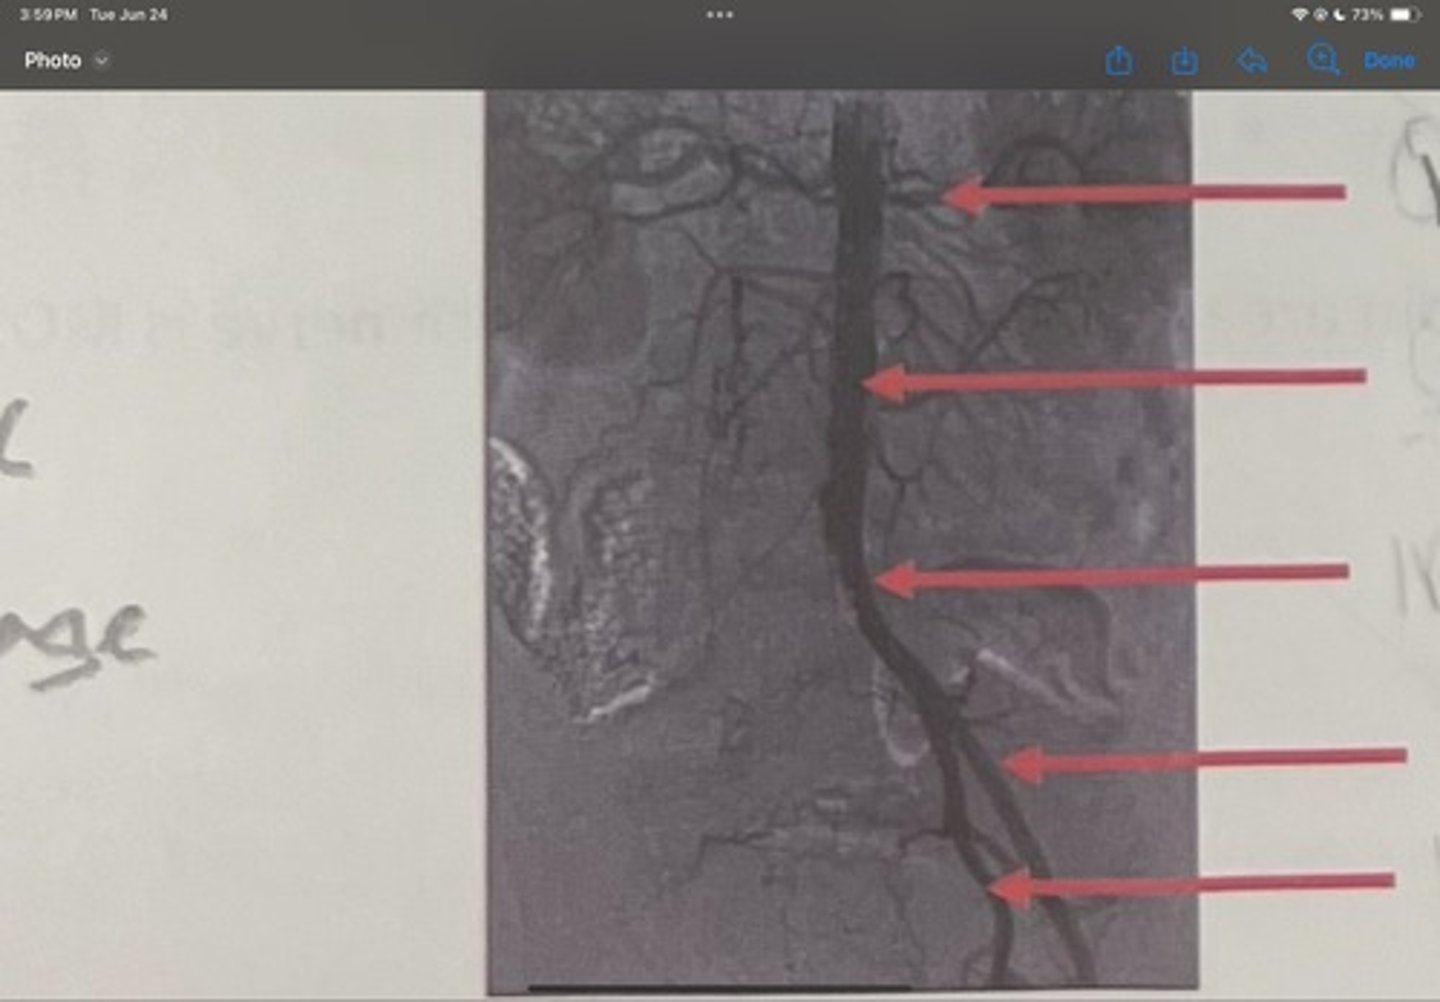

Renal artery

What is the 1st one

Abdominal aorta

What is the 2nd one

Common iliac artery

What is the 3rd one

External iliac artery

What is the 4th one

Internal iliac artery

What is the 5th one

right common iliac artery blockage

What is the pathology of the image